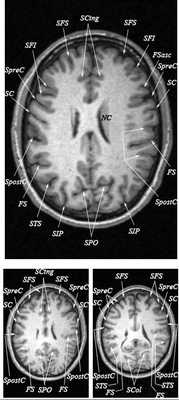

Знание анатомии мозга очень важно для правильной локализации патологических процессов. Ещё более важно оно для изучения самого мозга с помощью современных «функциональных» методов, таких как функциональная магнитно-резонансная томография (fMRI), и позитронно-эмиссионная томография. С анатомией мозга мы знакомимся ещё со студенческой скамьи и существует множество анатомических атласов, в том числе и поперечных сечений. Казалось бы, зачем ещё один? На самом деле, сравнение МРТ срезов с анатомическими приводит к множеству ошибок. Это связано как со специфическими особенностями получения МРТ изображений, так и с тем, что строение мозга очень индивидуально.

Представленная страница сайта основана на специальном изучении МРТ головного мозга здоровых лиц. Для этого изображения получали с минимальной величиной воксела (1 мм в каждом измерении), что исключало наслоения борозд. Каждая из структур прослеживалась в трёх реконструированных плоскостях путём её выделения с помощью компьютерной программы. Мы рассматривали различные анатомические варианты, что обсуждается в работе. В результате, учитывая вариабельность строения мозга, подобран условно «стандартный» мозг. Поскольку на сайте нереально представить 128 срезов в каждой из основных плоскостей, мы ограничились только каждым пятым срезом. Основные срезы в поперечной плоскости даны без наклона назад (угол 0º). Под ними для представления о изменении соотношения анатомических структур демонстрируются срезы, выполненные на тех же уровнях, но с наклонами назад -15º и -30º.

Список сокращений

Борозды

Междолевые и срединные

SC - центральная борозда

FS - Сильвиева щель (латеральная борозда)

SPO - теменно-затылочная борозда

SCing - поясная борозда

SpreC - предцентральная борозда

SFS - верхняя лобная борозда

SpostC - постцентральная борозда

SIP - внутритеменная борозда

STS - верхняя височная борозда

NC - хвостатое ядро

Поперечные (аксиальные) МРТ срезы головного мозга